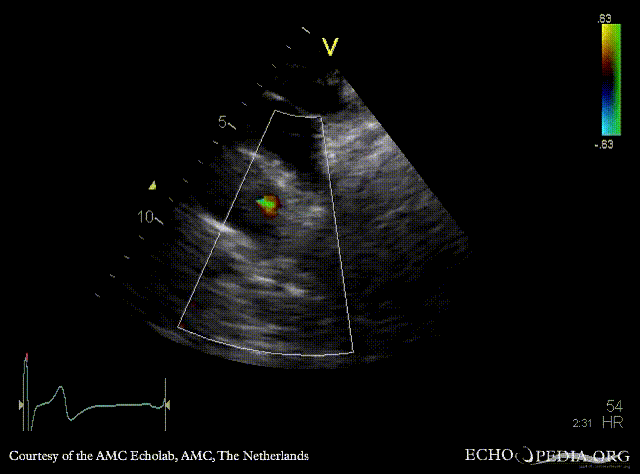

Open ductus Botalli

Courtesy of: AMC Echolab, AMC, The Netherlands

Suprasternal view with Color Doppler Pulsed-wave doppler signal of flow in ductus Botalli